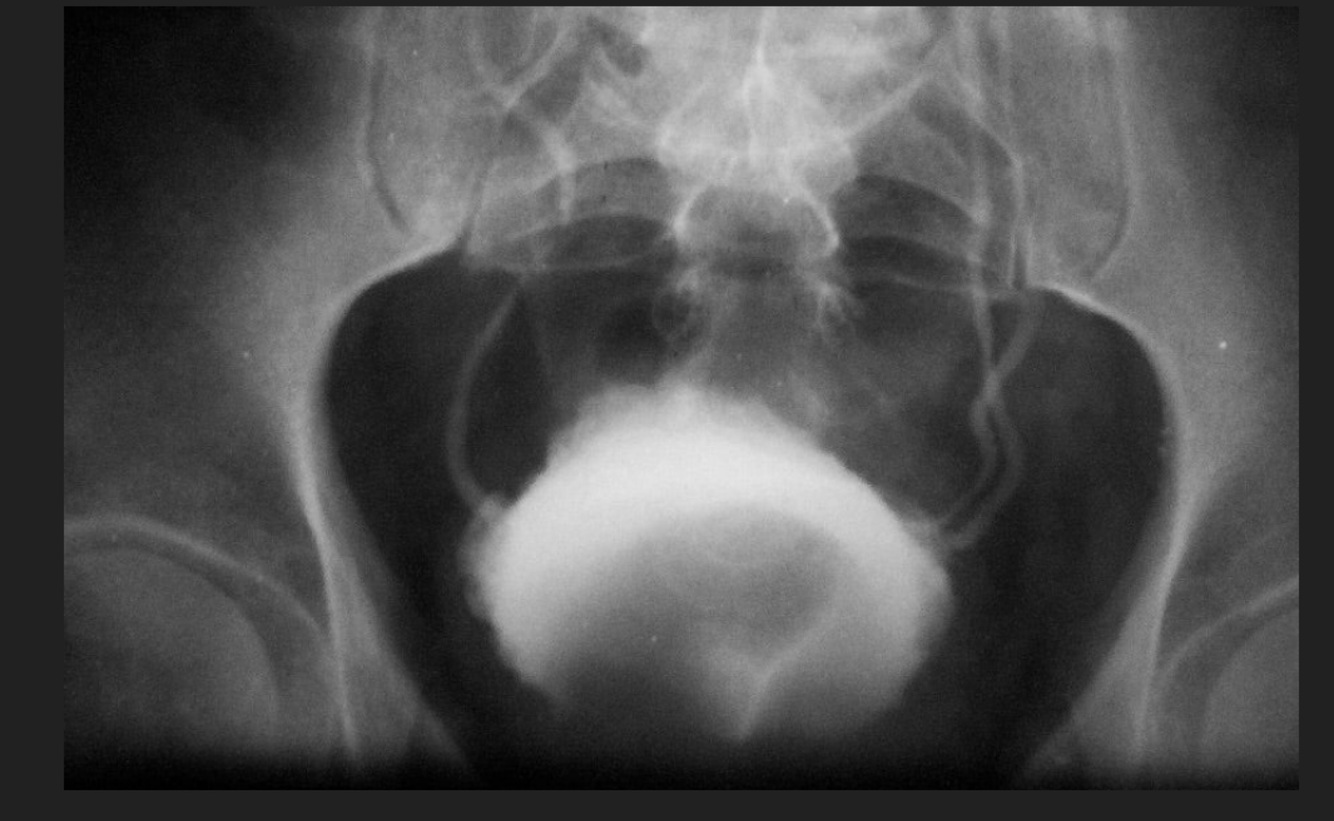

Cistograma con datos de:

A

Divertículos vesicales